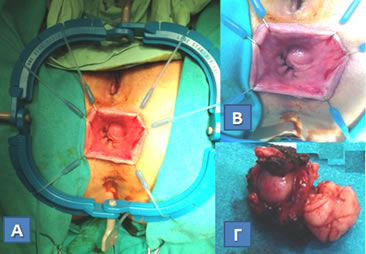

Εικόνα 6.

A. Χειρουργικό παρασκεύασμα ολικής ορθο-κολεκτομής σε ασθενή με σύνδρομο Gardner και κληρονομικό ιστορικό οικογενούς πολυποδιάσεως. Ανάπτυξη πολλαπλών πολυπόδων στο βλεννογόνο του παχέος εντέρου και δεσμοειδής όγκος στο μεσεντέριο του τελικού ειλεού (βέλη).

Β. Στην ίδια ασθενή δεσμοειδής όγκος στο μεσεντέριο του λεπτού εντέρου (βέλη). Οι δεσμοειδείς όγκοι αναπτύσσονται στο κοιλιακό τοίχωμα και στο μεσεντέριο, και, αν και χωρίς μεταστατικό δυναμικό, έχουν «κακοήθη συμπεριφορά», λόγω της τάσης τους να αυξάνονται σε μέγεθος προκαλώντας απόφραξη, ισχαιμία ή διάτρηση στο λεπτό έντερο. Είναι δύσκολα αντιμετωπίσημοι και η πολλές φορές αδύνατη χειρουργική αφαίρεσή τους πυροδοτεί τη γένεση επιθετικότερων δεσμοειδών όγκων. (Από το προσωπικό αρχείο του Γ. Θεοδωρόπουλου)